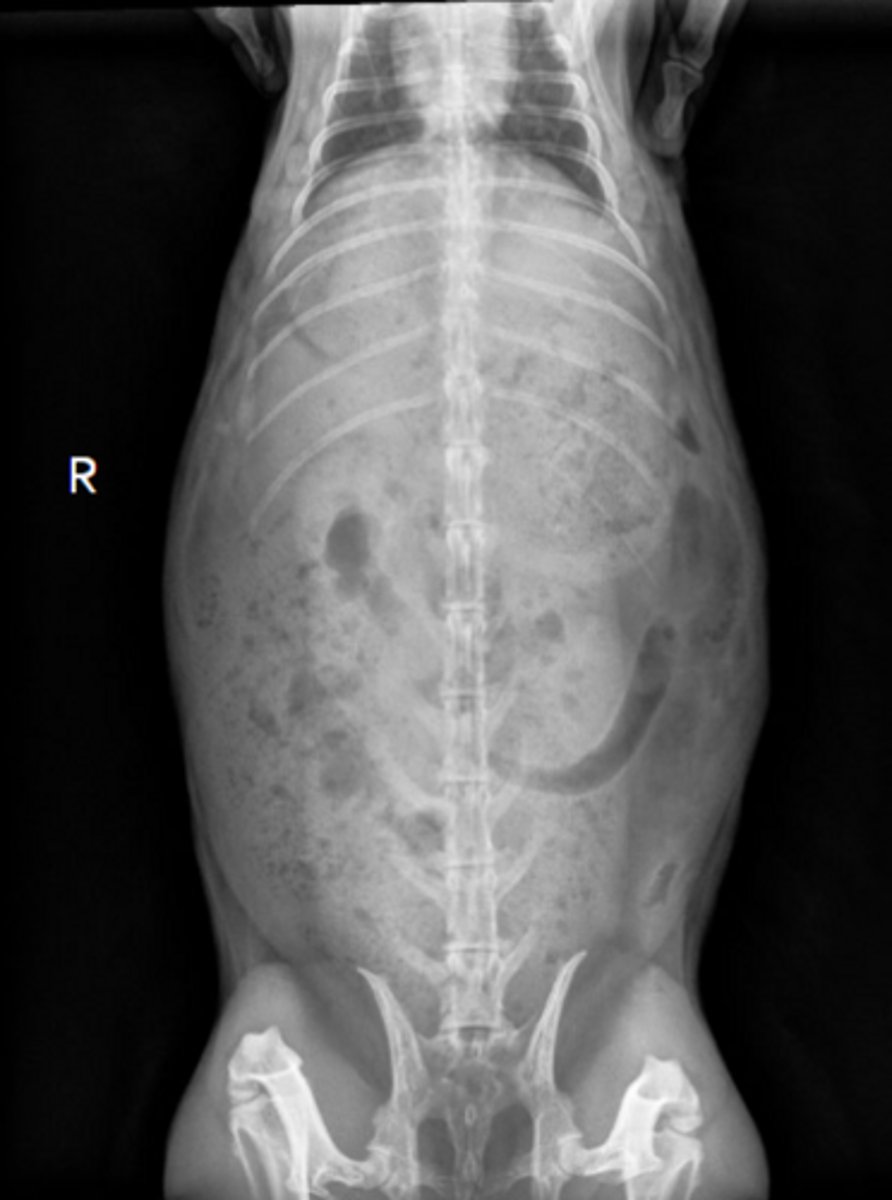

Normal

Is this a normal OR abnormal rabbit?

The caudal border of the stomach should not pass the caudal border of L2

How do you determine if the stomach is normal size on rabbit x-rays?

Dorsoventral

What radiographic view is this to image rabbits?

Lateral